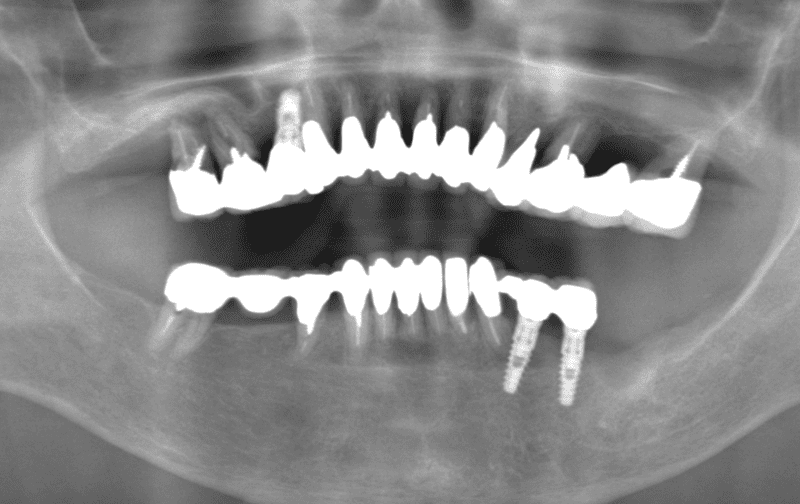

Before

After

主訴 左上のセラミックの歯の歯ぐきが下がって変色した歯が出てきて見た目が気になるのでやり直したい。 性別 女性 年齢 50代 症例概要・補綴専門医としての分析 ・50代女性

・左上5番にオールセラミッククラウンが装着されている。

左上4番にはインプラントによるオールセラミッククラウンが装着されている。

頬側の歯肉退縮が生じており歯頸部に黒変した歯質が露出して審美障害を生じている。

全体的な辺縁不適合が認められた。

セラミック咬合面には若干の咬耗が認められた。

左上5番頬側歯肉辺縁に発赤・腫脹は認められない。

エックス線から歯根に問題は認められなかった。

患者さんには、過度にブラッシングする習慣があり、ブラッシング圧とブラッシング時間のコントロールを指導した。

また、クレンチングの習癖があり、生活指導及びナイトガードの夜間使用をお願いしている。

これらのご指導・お願いが実施されることを前提に、咬合力の強くない女性であること、審美性を重視していることなどからモノリシックジルコニアクラウンではないジルコニアフレームにポーセレンを積層する方法、ジルコボンドクラウンにて再補綴することとした。